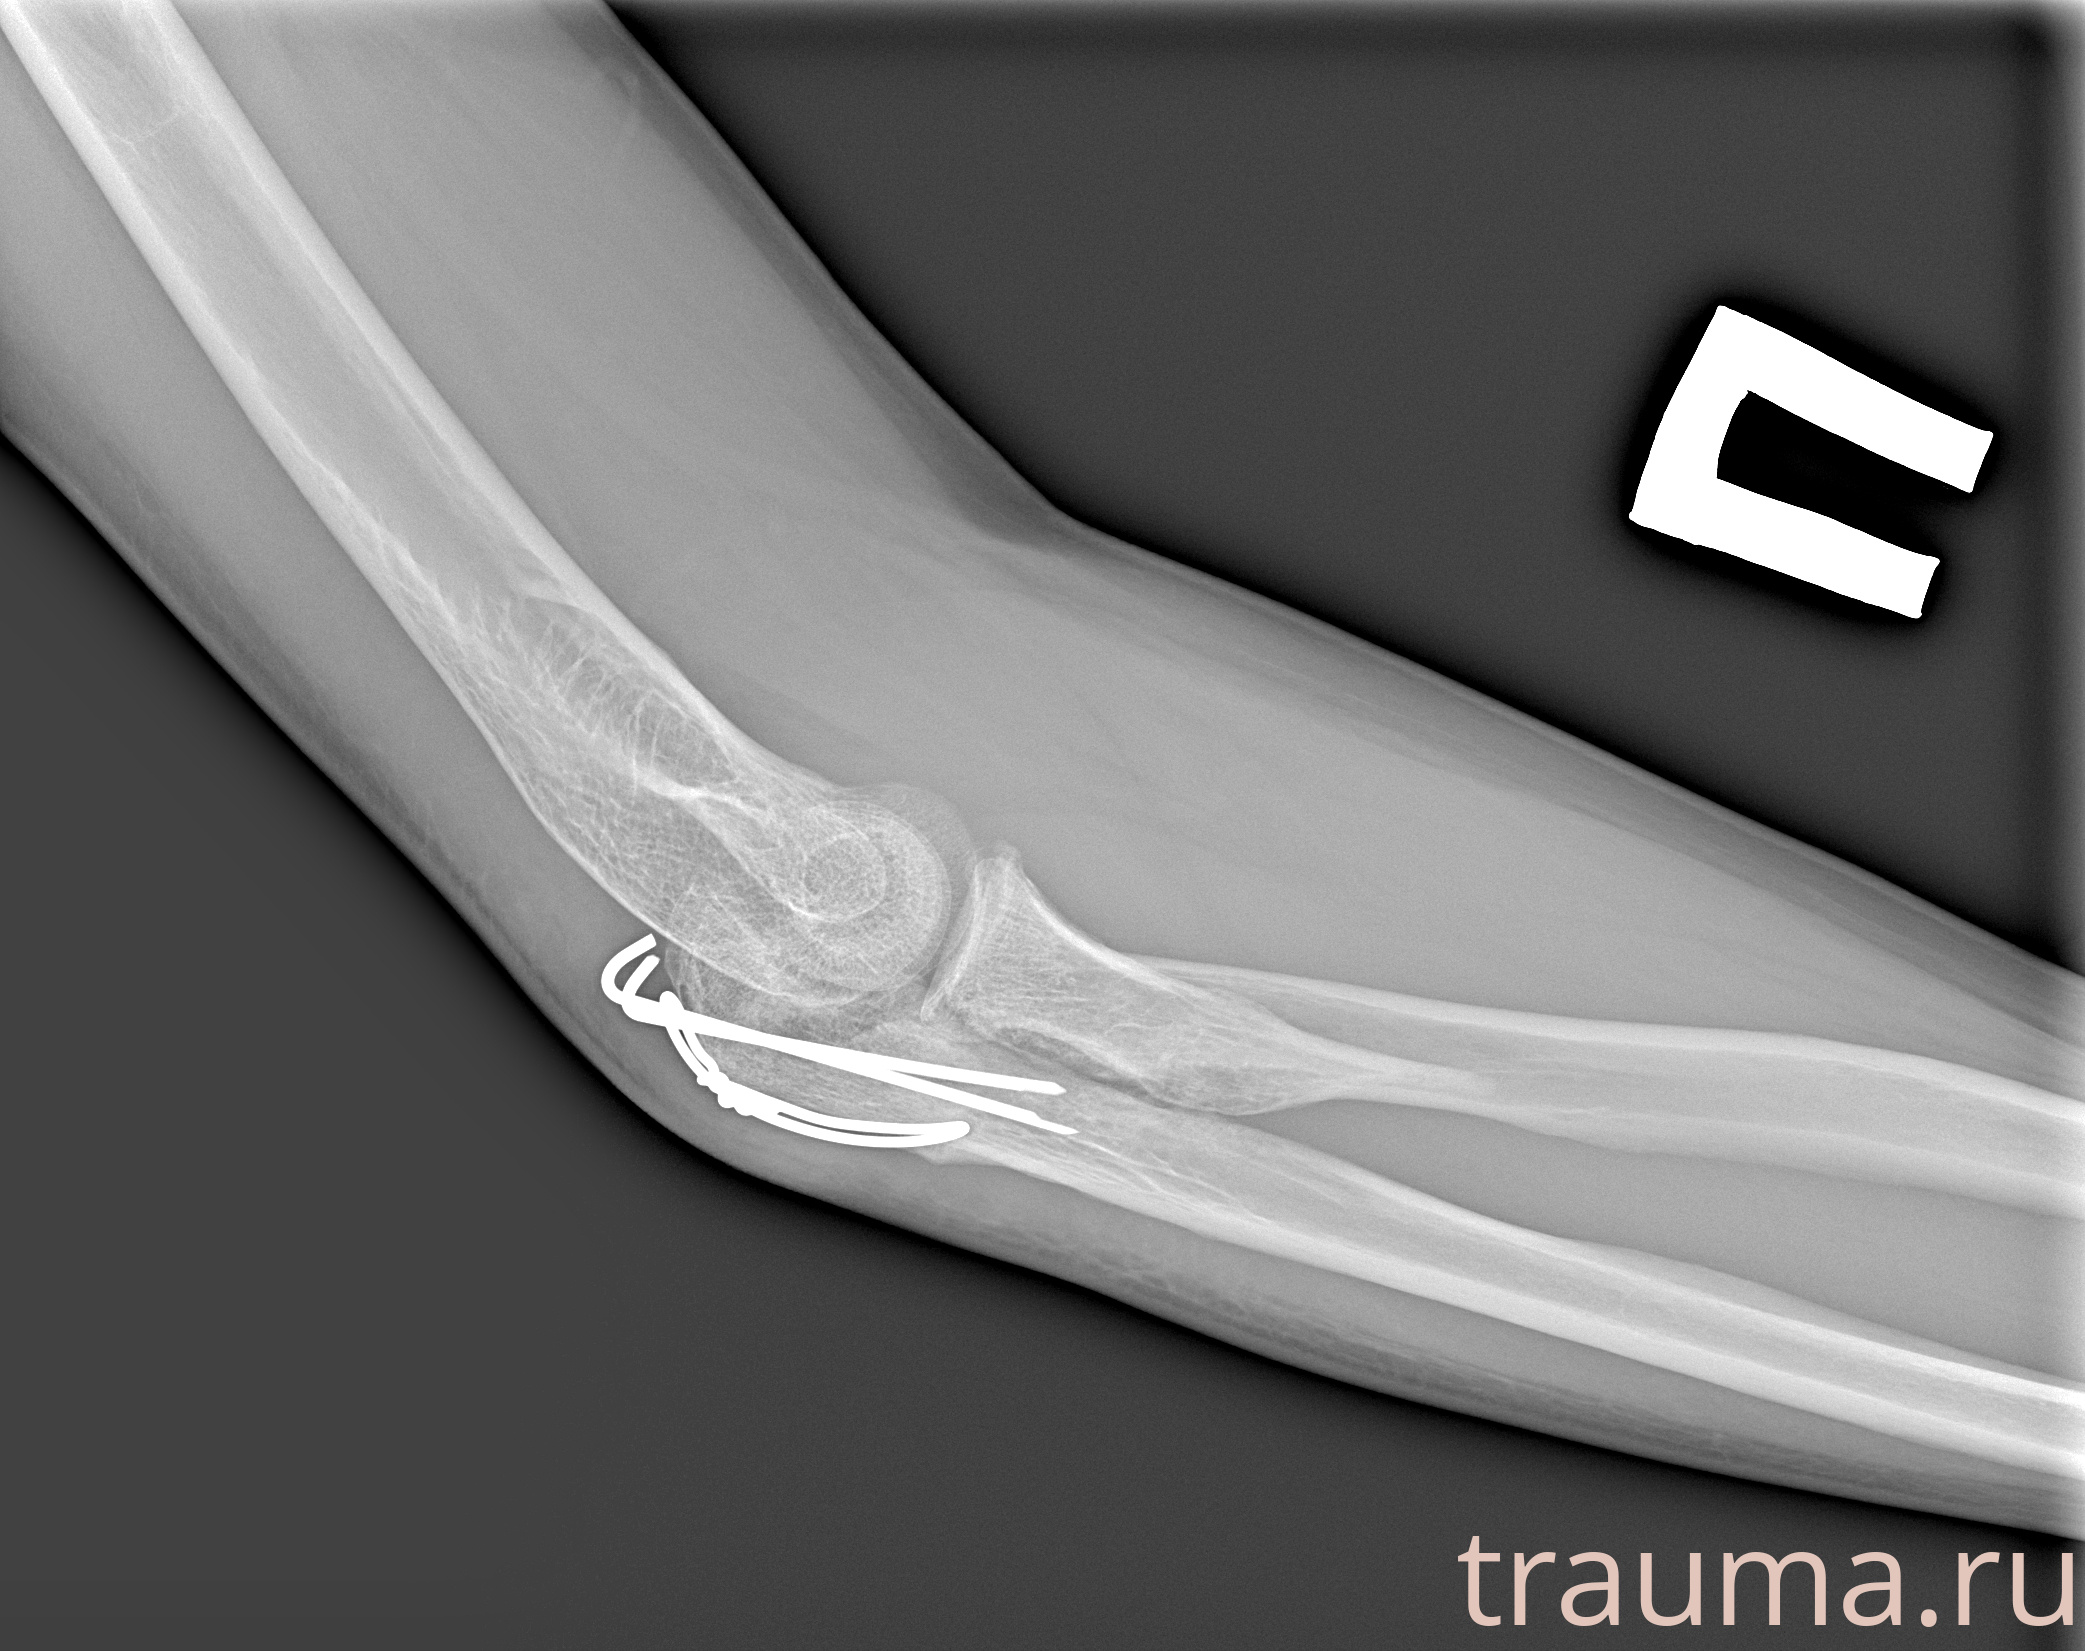

Рентген на дому: по вашему адресу приезжает врач-рентгенолог, травматолог-ортопед с мобильным рентгеновским аппаратом, проводит диагностику травмы или заболевания, делает необходимые рентгенограммы, дает рекомендации по дальнейшему лечению. Получить качественные снимки в домашних условиях возможно благодаря уникальной методике, разработанной МосРентген Центром для института  Склифосовского